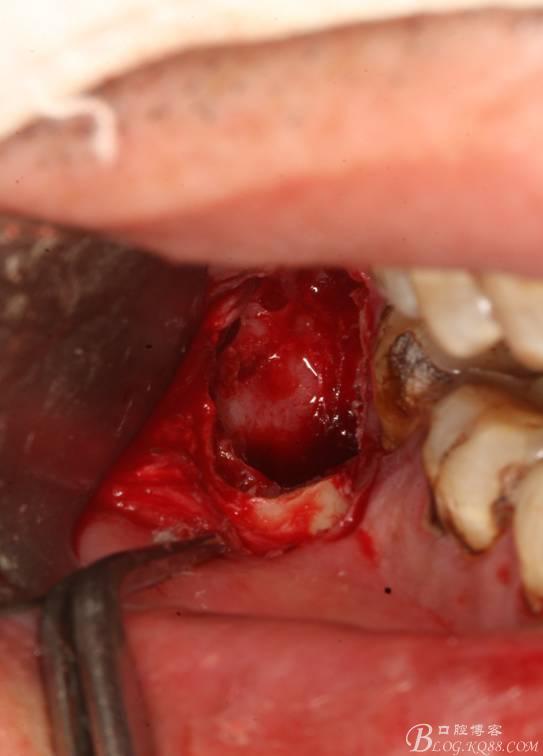

8.清理拔牙創(chuàng)

9.縫合